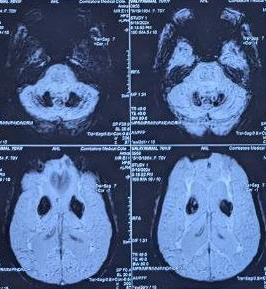

MRI brain was suggestive of coarse calcification in bilateral

basal ganglia, dentate nuclei and occipital gyri. She had low normal

serum calcium level. With elevated parathormone levels and vit-D3

Figure 2: MRI -SWI revealing bilateral symmetric hypointense signals (dark

spots) from basal ganglia and dentate nucleus of cerebellum

Imaging varies: While many cases report normal MRIs or nonspecific changes, some describe white matter changes or atrophy. Unusually, this case features coarse calcifications in basal ganglia, dentate nuclei, and occipital gyri, meeting radiological criteria for Fahr’s syndrome.[1,4]